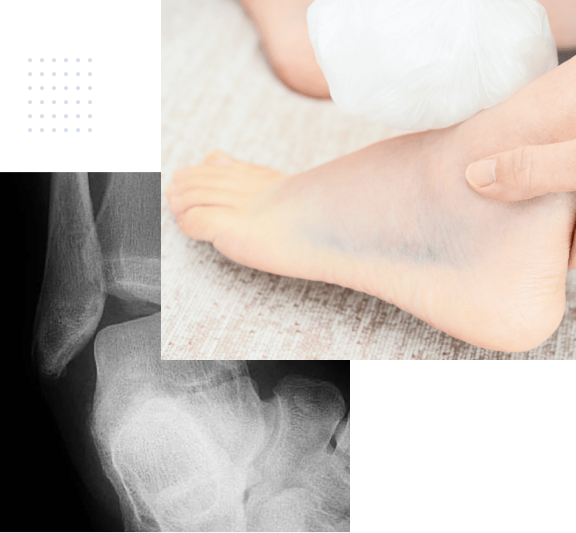

Fuss mit Röntgen

Pes Planovalgus (Knick-Senkfuss)

Der Knick-Senkfuss ist eine sehr häufige Fussdeformität und kann zu Schmerzen, Instabilität und Schwierigkeiten beim Gehen führen.

Die Längswölbung des Fusses ist abgeflacht, so dass der gesamte Fuss nach innen abkippt. Dies führt zu einer Überbelastung bestimmter Bereiche des knöchernen Skeletts, aber auch der Rückfusssehnen und stabilisierenden Bänder auf der Innenseite von Mittel- und Rückfuss. Die Deformität kann zu Schmerzen und Beschwerden führen, insbesondere bei längerem Stehen oder Gehen.